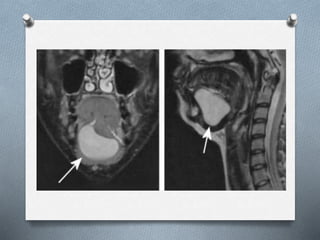

La ránula es una lesión mucocele que se forma unilateralmente en el piso de la boca, asociada al conducto de Wharton o de Bartolino. Puede ser causada por traumatismos u obstrucciones. Se presenta como una masa traslúcida, de color normal o morado-rojizo, mayor a un mucocele común. Su diagnóstico se realiza clínicamente y puede confirmarse con tomografía computarizada o resonancia magnética. Los tratamientos incluyen marsupialización, escisión de la glándula